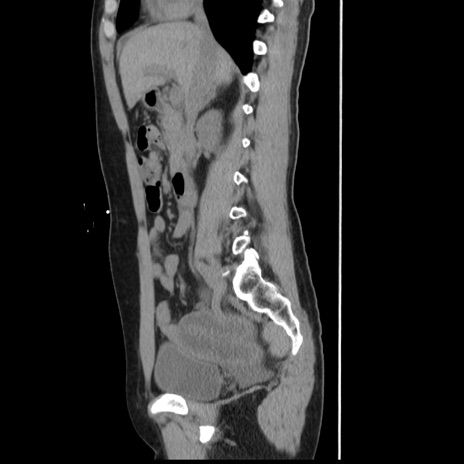

横断像

【症例】 50歳代女性

【主訴】 腹痛

【現病歴】前日生レバーを食べた。今朝に排便あり。 昼前に突然発症の腹痛を生じ、当院救急外来を受診した。

【既往歴】 子宮筋腫にてで子宮全摘後

【身体所見】 意識清明、腹部:平坦、軟、下腹部やや左を中心に圧痛・反跳痛あり、筋性防御あり

【データ】WBC 7800、CRP 0.07